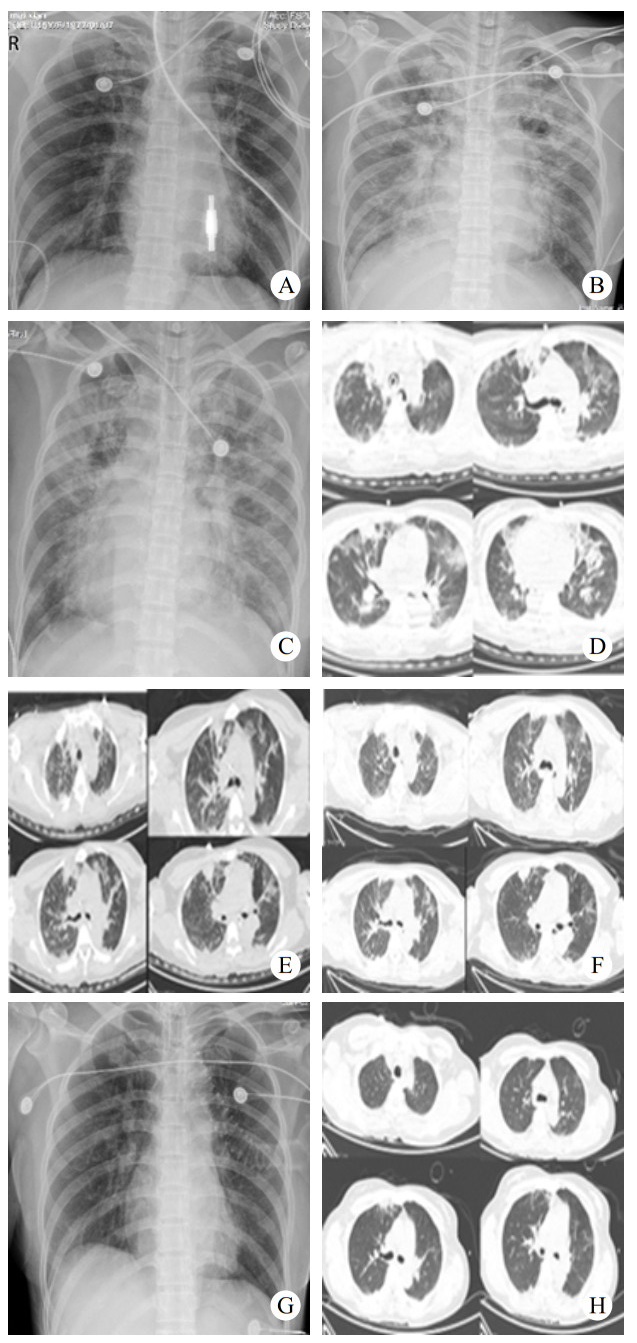

2 结果入院时实验室查急诊血清胆碱酯酶(cholinesterase, ChE):小于196 U/L。血常规:白细胞(white blood cell, WBC)9.24×109/L,中性粒细胞百分比(neutrophil, NEUT%)88.3%,PLT 230×109 /L,红细胞(red blood cell, RBC) 4.08×109/L血红蛋白(hemoglobin, Hb)128 g/L。动脉血气分析:酸碱度(potential of hydrogen, pH)7.247,二氧化碳分压(partial pressure of carbon dioxide, PCO2)30.2 mmHg,氧分压(partial pressure of oxygen, PaO2)93.8 mmHg(呼吸机辅助通气下吸氧浓度为50%),氧合指数284.3%,血钠(Na+) 141.1 mmol/L,血钾(K+) 3.25 mmol/L,乳酸(lactic acid, Lac)8.35 mmol/L,血糖16.05 mmol/L,碳酸氢根12.8 mmol/L,碱剩余-13.2 mmol/L。床旁快速心肌酶:心脏特异性肌钙蛋白Ⅰ(cardiac troponin, cTnⅠ)0.17 ng/mL,肌红蛋白(myoglobin, Myo)123.6 ng/mL,肌酸激酶同工酶(creatine kinase, myocardial-type, CK-MB)17.83 ng/mL。床旁NT-proBNP: 106 ng/L,肝功能:天门冬氨酸氨基转移酶(aspartate aminotransferase, AST)162 U/L,丙氨酸氨基转移酶(alanine aminotransferase, ALT)86 U/L,肌酸激酶196 U/L,乳酸脱氢酶(lactate dehydrogenase, LDH)302 U/L。肾功能:肌酐(creatinine, CREA)104 μmol/L,尿素氮4.84 mmol/L。凝血常规:PT 12.9 s,APTT 34.7 s。新冠病毒抗体阴性。急性感染三项:白介素6 1 148.0 pg/mL,降钙素原(procalcitonin, PCT)0.688 ng/mL,超敏C反应蛋白0.78 mg/L。后期上述指标变化见图 1。床旁胸片显示,(1)双肺纹理增多、增粗、模糊,双肺感染可能;(2)左侧胸腔少量积液可能。见图 2。住院期间讨论CT示:硬膜下积液,见图 3。

| 注:A: 2022-07-16床旁胸片示双肺纹理增多;B:2022-07-18床旁胸片示双肺感染,间质性肺水肿可能;C:2022-07-19床旁胸片示双肺感染;D:2022-07-21胸部CT示①双肺感染、间质性肺水肿可能;②右肺上中叶及左肺上叶结节状模糊影,炎性可能,请复查;③双侧胸腔积液,双肺下叶部分不张;E:2022-07-24胸部CT示对比2022-07-21①双肺散多发感染,双肺散在肺组织不张、部分实变,大致同前;②间质性肺水肿,较前加重。③双侧胸腔少量积液,大致同前;F:2022-07-26胸部CT示对比2022-07-24 CT,①双肺散多发感染,双肺散在肺组织不张、部分实变,同前;②间质性肺水肿,同前;③右肺上叶尖段磨玻璃结节,建议复查;④双肺上叶、右肺下叶多发实性结节,考虑炎性,建议复查;⑤双侧胸腔少量积液,较前减少;G:2022-07-29床旁胸片示双肺散在多发感染;H:2022-08-01对比2022-07-26 CT:①双肺散多发感染,双肺散在肺组织不张、部分实变,较前稍减轻;②间质性肺水肿较前减轻 图 2 患者住院期间肺部主要影像学变化 |